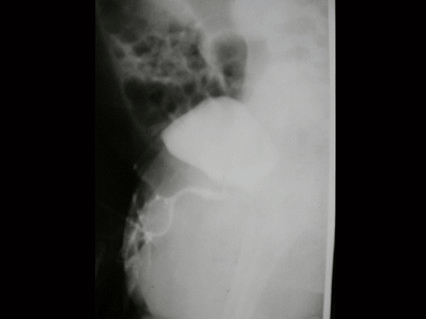

5.

男,4个月,阴茎、排尿异常4个月,行尿道造影如图所示,最可能的诊断是 ( )

A.

正常尿道

B.

尿道瓣膜形成

C.

尿道下裂畸形

D.

尿道憩室

E.

尿道重复畸形